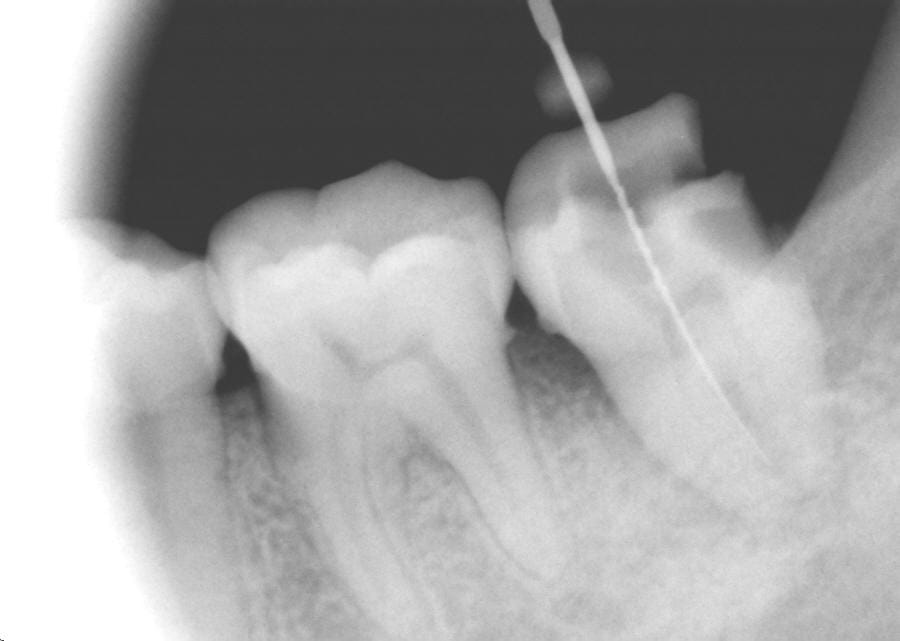

Bon allez, qq infos

C'est une 7, ouverture de chambre car abcès +++ pour soulagement immédiat donc pas de digue, ouverture buccale rendant impossible de tenir la turbine verticalement, vision directe impossible bien sûr...

Alors perfo, pas perfo, j'hésite... ;-)

le plafond , n'a pas été ( totalement ) enlevé , ç est qu'il y a une 3eme racine ?

pcq s'il ne peut tenir correctement la turbine , alors un giro , je ne te dis pas , donc ç est que l'accès a été facile , ors sans déposer le plafond ,.....